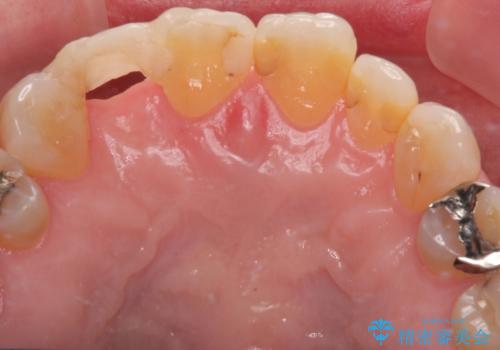

最新の症例